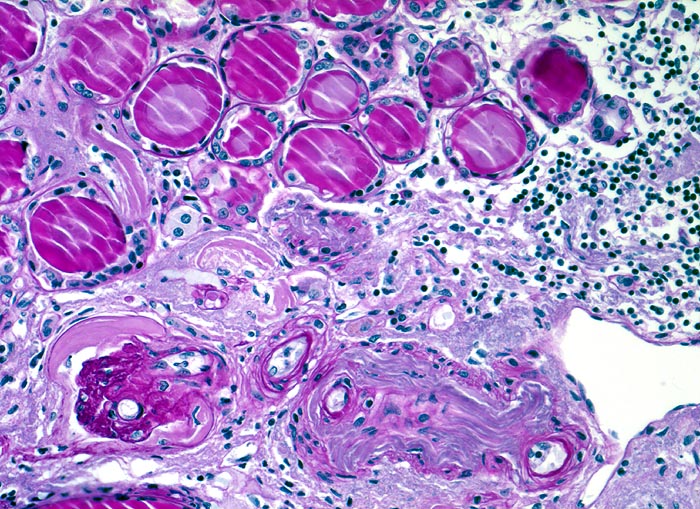

Histologisch finden sich neben völlig unverändertem Parenchym herdförmige Infiltrate aus Lymphozyten, Plasmazellen, Histiozyten und bei akutem Schub zusätzlich neutrophile Granulozyten. Das destruierte Gewebe wird durch Granulationsgewebe im Intersititum organisiert. Gruppen erhaltener Tubuli mit vergrössertem Durchmesser und abgeflachtem Epithel gefüllt mit Harnmukoid (=Tamm-Horsfall Protein und/oder IgA) bilden Pseudostrumaherde ( 1793). Diese sind ein wichtiger Hinweis aber kein Beweis für chronische Pyelonephritis. Bei Kindern finden sich oft zusätzlich Lymphfollikel. Glomeruli kollabieren und zeigen eine konzentrische periglomeruläre Fibrose. Oft findet sich eine Arteriolosklerose und eine adaptative Intimafibrose grösserer Arterien. Obligat findet sich eine schwere chronische Pyelitis sowie eine Fibrose von Nierenbecken und Nierenmark. Bei fortgeschrittener bilateraler Nierenschädigung kommt es zum Auftreten einer Überlastungsglomerulopathie, die meist unter dem Bild einer segmentalen fokalen Glomerulosklerose in Erscheinung tritt.